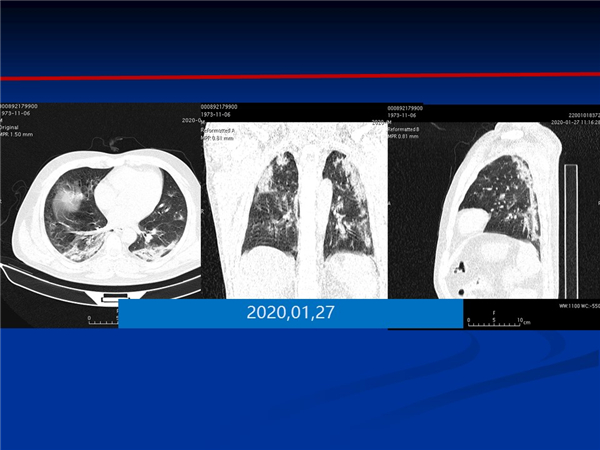

【病例分享】新型冠狀病毒感染肺部CT影像4例(常德市第一人民醫(yī)院)